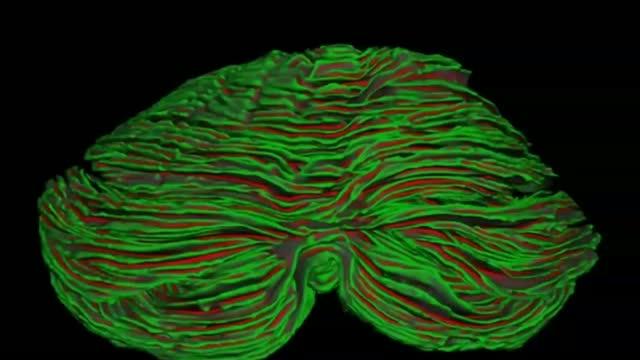

video: Neuroscientist Martin Sereno, director of the SDSU MRI Imaging Center, and his collaborators discovered the surface area of the cerebellum is equal to 80% of the cerebral cortex's surface area, enabling further understanding of the landscape of the brain.

San Diego State University MRI Imaging Center

Collaborating with imaging and cerebellum experts from the United Kingdom, Netherlands and Canada, Sereno used customized open source FreeSurfer software that he originally developed with colleagues while at the University of California San Diego to computationally reconstruct the folded surface of the cerebellum. The software also unfolds and flattens the cerebellar cortex so as to visualize it to the level of each individual folia -- or thin leaf like fold.

A pioneer in brain imaging who has leveraged functional MRI to uncover visual maps in the brain, Sereno found that when the cerebellum is completely unfolded, it forms a strange "crepe" four inches wide by three feet long. The findings were published this week in a study in PNAS (Proceedings of the National Academy of Sciences).